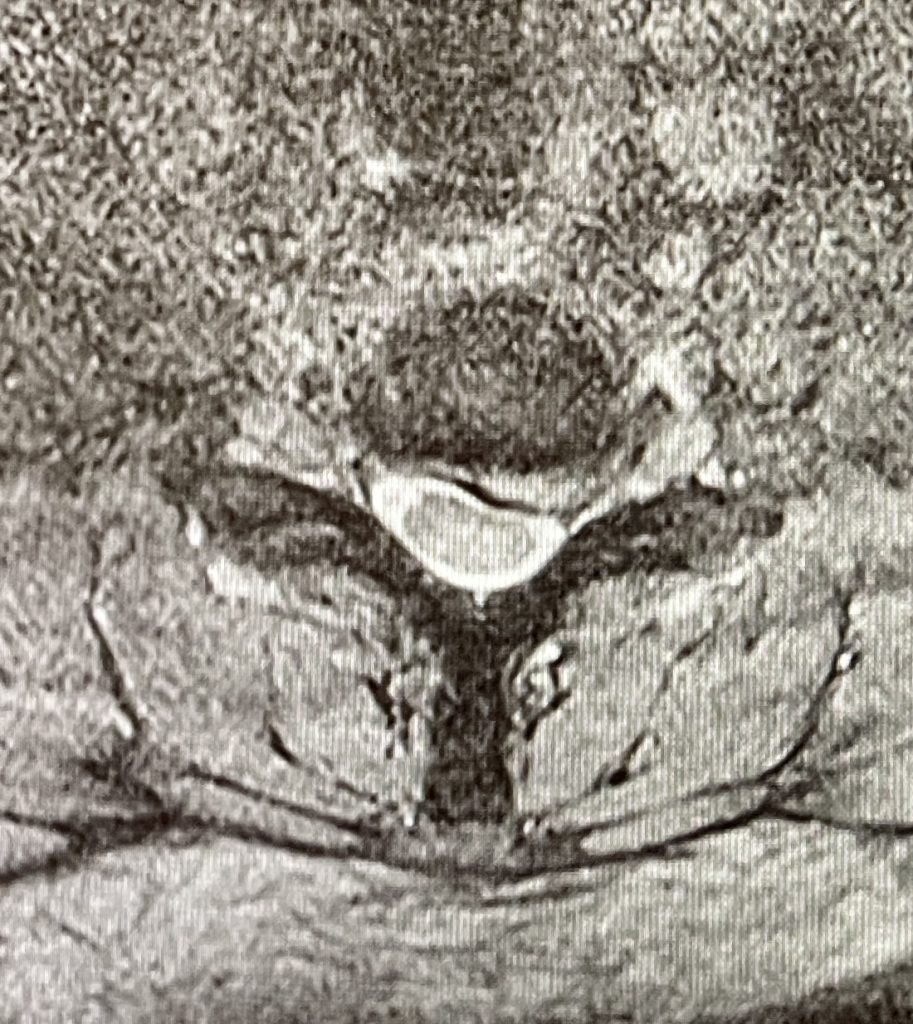

Hernia discal Cervical

El tratamiento quirúrgico de la hernia de disco cervical, implica la retirada del fragmento de disco migrado , que está comprimiendo e irritando la raíz nerviosa.

La vía anterior es la técnica habitualmente más utilizada, se realiza con una incisión de unos 3-4 cm en la parte anterolateral del cuello, y desde la misma se aborda y retira el disco lesionado junto con la hernia. De este modo se descomprime la raíz nerviosa en el canal medular.